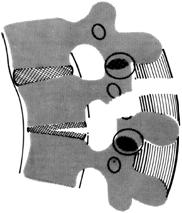

3. Сгибательно-дистракционное повреждение (повреждение по типу ремней безопасности, seat-belt повреждение)

Механизм повреждения - резкое сгибание с осевой тягой верхнего и нижнего сегментов позвоночника при фиксированном центральном отделе. Зона повреждения – средняя и задняя колонны позвонков, возможно повреждения передней. Эти повреждения являются механически нестабильными. Различают следующие варианты повреждений: А – одноуровневое чрезпозвоночное повреждение. В – одноуровневое с повреждение заднего связочного аппарата. С – двухуровневое костное повреждение средней колонны. D – двухуровневое повреждение с переломом дуги и дискового аппарата.

Рис. 3. Варианты сгибательно-дистракционных повреждений по F.Denis

А – одноуровневое костное повреждение (перелом Chance),

В – одноуровневое лигаментозное повреждение,

С - двухуровневое чрезкостное повреждение,

Д - двухуровневое повреждение связочного аппарата средней колонны.